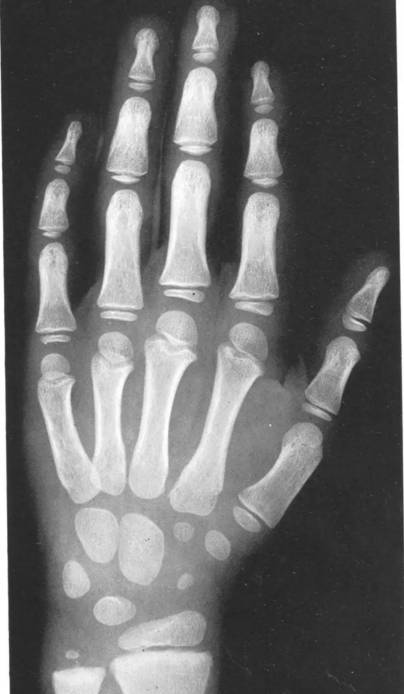

首先,生长发育可用两个“年龄”来表示,即生活年龄(日历年龄)和生物年龄(骨龄)。骨龄是骨骼年龄的简称,借助于骨骼在X光摄像中的特定图像来确定。在了解人的骨龄情况时,通常要拍摄人体手腕部的X光片,在这里要选择弱手,也即左手,如遇左撇子则相反。医生通过X光片观察左手掌指骨、腕骨及桡尺骨下端的骨化中心的发育程度,来确定骨龄。

下面给大家看看从出生到成人时骨龄变化时得X光片,拿一个男孩的左手拍摄的X光片为例,就可以看出整体的骨龄变化。

新生儿左手的X光片↓,这时腕骨,掌骨,和指骨的骨垢线是一生中最长的时候。